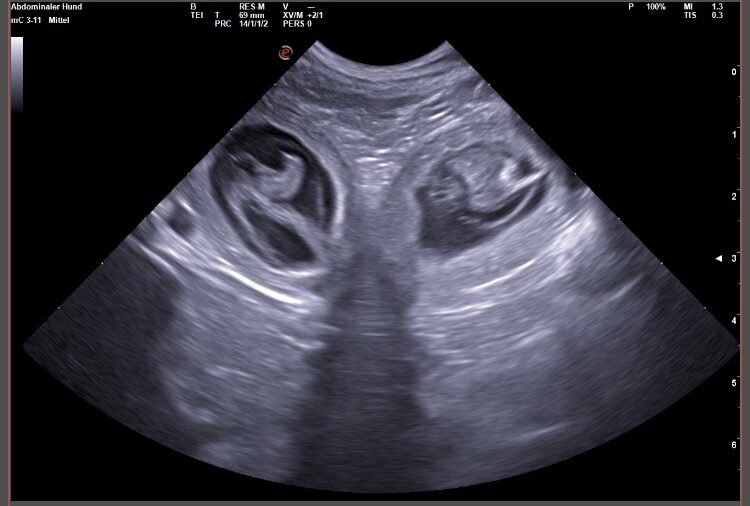

Wir waren erfolgreich und konnten Fruchtanlagen mit schlagenden Herzen sehen. Wir gehen zum aktuellen Zeitpunkt wieder von einem größeren Wurf aus. Daykos und Dorias Rendevouz war also sehr vielversprechend!

Hier zeigen wir euch einige der kleinen gefüllten Fruchtblasen mit Inhalt und schlagenden Herzen. Da wir kurz vor Ostern mit der Geburt rechnen, nennen wir sie „Ostereier“ 🙂